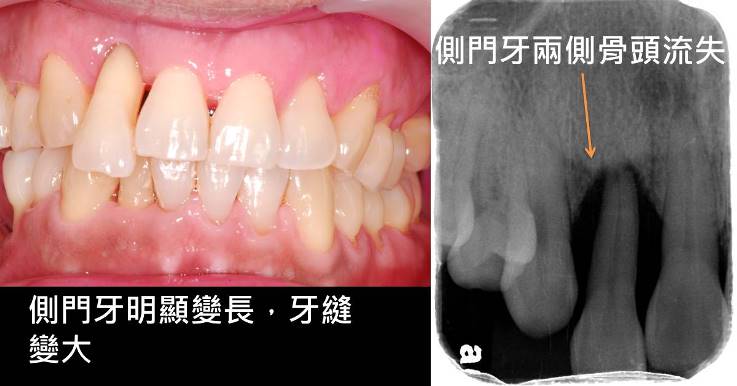

當細菌的破壞繼續進展而造成牙齒周邊支持的骨頭流失後,就稱為「牙周炎」,隨著骨頭的流失後,牙齦就會跟著萎縮、牙縫變大、支持的骨頭破壞增大後,也可能出現牙齒動搖、咀嚼變的比較沒有力量。

● 牙齒位移、牙齒看起來越來越長

● 牙縫變大